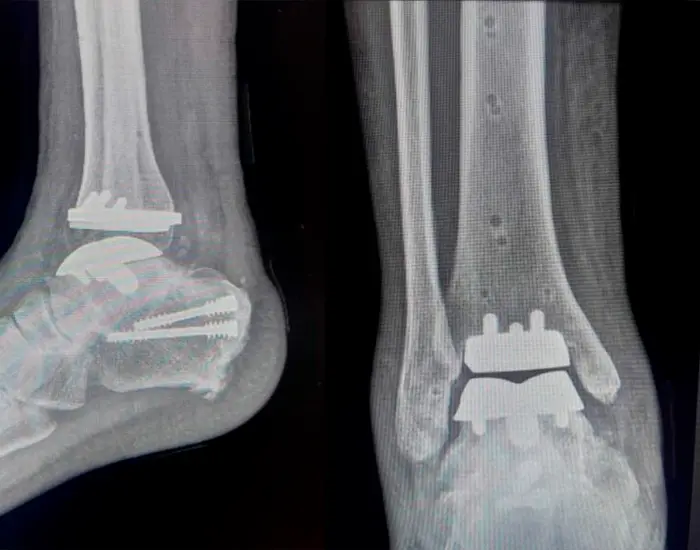

A cirurgia de prótese total de tornozelo ainda é considerada rara no Brasil. Trata-se de um procedimento altamente especializado, indicado para pacientes com desgaste grave da articulação do tornozelo (artrose tibiotalar), muitas vezes com dor crônica intensa e perda funcional significativa. Em Santo André, a paciente que passou por esse tipo de cirurgia está sendo reabilitada pela equipe da Reaxis, em um dos primeiros casos do tipo na região.

A prótese é uma substituição da articulação entre a tíbia e o tálus por componentes metálicos e de polietileno, que permitem ao paciente voltar a se movimentar com menos dor e maior estabilidade. Ao contrário da artrodese (fusação do tornozelo), a prótese busca manter o máximo de mobilidade possível na articulação.

A paciente em reabilitação na Reaxis foi submetida à primeira cirurgia de prótese total de tornozelo da cidade de Santo André. Seu quadro clínico exigia solução definitiva para dor crônica e perda funcional.